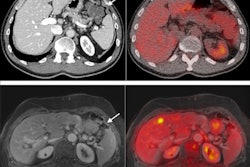

Comparison between PET+MRI (A) and PET/MRI (B); axial and coronal plane, PET alone and co-registered on MRI. The subject is a 17-year-old female with drug-resistant epilepsy since the age of 2 years; nocturnal frontal seizures (3 times per night), left frontotemporal ictal onset, negative MRI (3 tesla). Her first PET examination co-registered on MRI at 11 years considered negative; PET/MRI six years later, showing a focal hypometabolism involving the posterior part of the left orbitofrontal cortex, relative involvement of the adjacent cortex (gyrus rectus, anterior part of the left inferior frontal gyrus) and the temporal pole. This hypometabolism was retrospectively found on the previous PET but remained inconclusive. Note that the co-registration was imperfect on this examination, whereas it was almost perfect on the PET/MRI, allowing a better confidence for the visual analysis. The patient was operated on without invasive monitoring despite a negative MRI scan. Surgery was based on a PET/MR guided cortical resection, including the hypometabolic orbitofrontal cortex and the adjacent inferior frontal gyrus, in front of Broca area. FCD type 2 A was found in the cortical specimen. The patient has been seizure-free for two years and the use of antiepileptic drugs greatly reduced. Image courtesy of Epilepsy Research.In addition, hybrid PET/MRI resulted in changes in surgical decisions for 10 patients (40%), consisting of avoiding invasive monitoring in six patients and modifying the planning in four others, the researchers found.